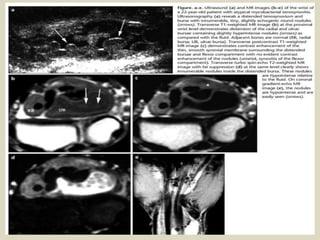

Subcoracoid bursitis, (1a, 1b, 1c) Three sagittal fat-suppressed T1-weighted images extending lateral to medial.

Subcoracoid bursitis.